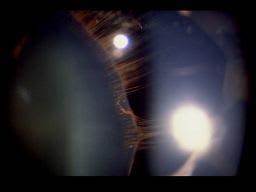

Dislocation of the Crystalline Lens

The crystalline lens normally lies behind the iris and in front of the vitreous, held in its position by the zonules. These photos show a dislocated lens, or ectopia lentis, which occurs when the lens is not in its normal position. When a lens is decentered but remains in the papillary area, it is referred to as subluxated. It is estimated that greater than 25 percent of zonular fibers must be disrupted for subluxation to occur1. Patient symptoms of lens subluxation include decreased vision, monocular diplopia, progressive myopia, and marked astigmatism.

A luxated lens is defined as complete displacement of the crystalline lens from the papillary aperture, implying complete disruption of zonular fibers. The lens may be dislocated forward into the anterior chamber or posteriorly into the vitreous.